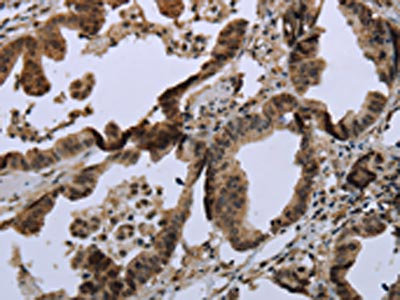

• The image on the left is immunohistochemistry of paraffin-embedded Human liver cancer tissue using CSB-PA557048(MAPKAPK2 Antibody) at dilution 1/20, on the right is treated with synthetic peptide. (Original magnification: ×200)

• The image on the left is immunohistochemistry of paraffin-embedded Human colon cancer tissue using CSB-PA557048(MAPKAPK2 Antibody) at dilution 1/20, on the right is treated with synthetic peptide. (Original magnification: ×200)